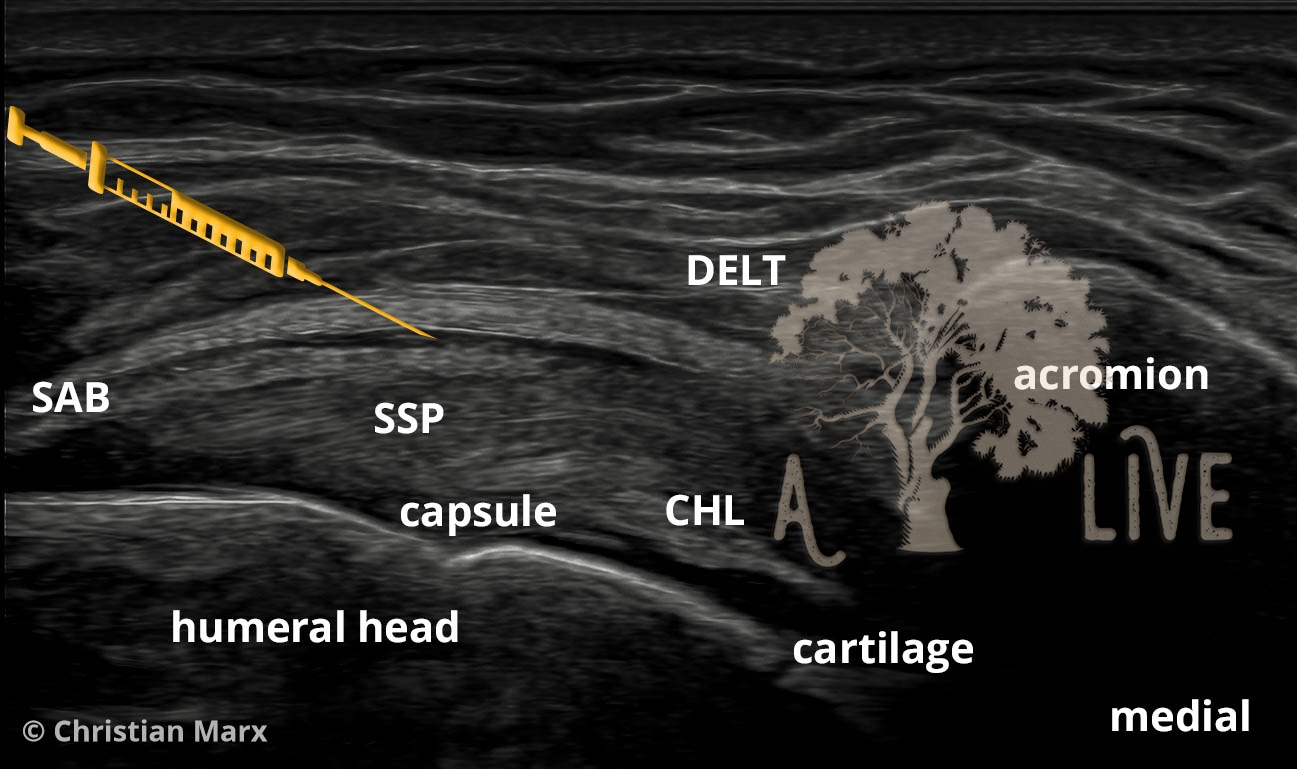

Injections

injections around the shoulder